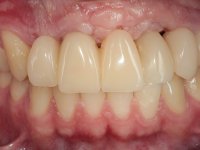

Paciente do sexo masculino, com 22 anos de idade e não fumador. Apresentou-se na consulta 6 meses após um acidente de viação em que perdeu os dentes 21, 22, 23 e 24. Os dentes 12 e 11 apresentavam mobilidade grau 3 apresentando-se também com extracção indicada. A arquitectura gengival da zona desdentada apresentava-se retraída e planificada.

O paciente foi observado conjuntamente e a dúvida que surgiu de imediato foi se seria possível com a regeneração óssea a efectuar poder ser reabilitada naturalmente a zona das papilas interdentárias. Nesse sentido foi feito um enceramento de diagnóstico que contemplaria as duas hipóteses, utilizando ou não a cerâmica gengival. A confecção desse enceramento foi fundamental para expor ao paciente a dificuldade da reabilitação. O wax-up deu origem a um mock-up que foi aprovado pelo paciente e que simultaneamente serviu de guia imagiológica. O caso foi planificado cirurgicamente e realizada uma guia cirúrgica com que foram colocados os implantes. Após 10 semanas foi feita a 1ª impressão para confecção da ponte provisória. Foram criados os primeiros perfis de emergência na gengiva artificial e foi digitalizado o modelo. Por processo de CAD-CAM foi confeccionada uma ponte provisória aparafusada baseada no enceramento de diagnóstico. A ponte trabalhou durante 8 semanas os tecidos moles que foram fielmente copiados numa impressão com técnica de moldeira aberta. Os transferes foram individualizados com resina composta para copiarem fielmente os perfis de emergência criados pela ponte provisória. Confeccionado o modelo de trabalho definitivo, foi realizada uma infra-estrutura em zircónio seguindo a orientação do enceramento de diagnóstico. O assentamento da infra-estrutura foi testado em boca e simultaneamente foi novamente impressionados os tecidos moles com um silicone fluido. Nessa consulta foi feito o levantamento da cor. Os dentes 13 e 23 apresentavam uma saturação anormalmente forte que resolvemos não valorizar, optando por privilegiar a relação com o sector antero-inferior. Foi realizada uma nova gengiva artificial com a impressão que acompanhou a impressão de arrasto com a infra-estrutura. Após a colocação da cerâmica na infra-estrutura foram coladas as meso-estruturas. O trabalho final foi aparafusado lentamente permitindo a adaptação dos tecidos moles.